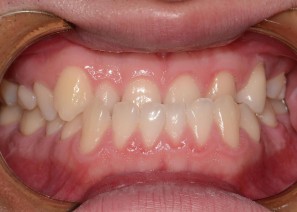

Before

After